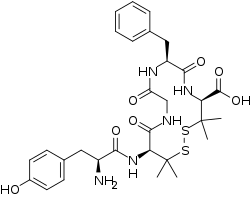

Opioid peptides

Others / unknown

- Adrenorphin

- Amidorphin

- Biphalin

- Casokefamide

- Casomorphins

- Cytochrophin-4

- DALDA (Tyr-D-Arg-Phe-Lys-NH2)

- Deltorphin I

- Deltorphin II

- Deprolorphin

- Dermorphin

- DPDPE

- Frakefamide

- Gliadorphin

- Gluten exorphins

- Hemorphin-4

- Metkefamide

- Morphiceptin

- Nociceptin

- Octreotide

- Opiorphin

- Rubiscolin

- Soymorphins

- Spinorphin

- TRIMU 5

- Tynorphin

- Valorphin

- Zyklophin

Structures

| Other or unknown opioid peptides | ||||

|---|---|---|---|---|

Adrenorphin Adrenorphin |

Amidorphin Amidorphin |

Casomorphin Casomorphin |

DALDA DALDA |

|

DPDPE DPDPE |

Endomorphin-1 Endomorphin-1 Endomorphin-2 Endomorphin-2 |

Gliadorphin Gliadorphin |

Morphiceptin Morphiceptin | |

Nociceptin Nociceptin |

Octreotide Octreotide |

Opiorphin Opiorphin |

Rubiscolin Rubiscolin |

TRIMU 5 TRIMU 5 |